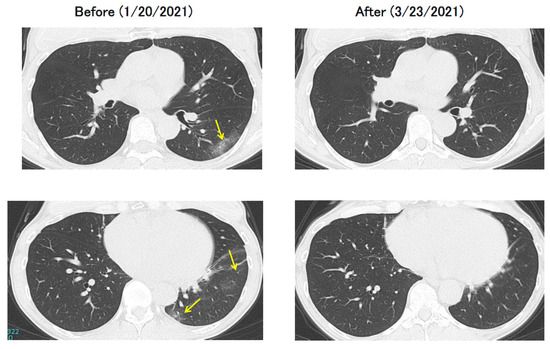

Chest CT showed emphysematous and old inflammatory changes that may have been present prior to SARS-CoV-2 infection (Figure 5). This case shares similarities with the case presented in the national examination at the beginning of this article in which the patient was an older adult man with a history of heavy smoking. Although the risk of serious illness appears to be high, the only symptom of COVID-19 was a mild common cold. However, the patient was forced to recuperate in a hotel without undergoing oral surgery, which he could have undergone. Thus, after SARS-CoV-2 was replaced by the Omicron strain, the symptoms of COVID-19 were either asymptomatic or extremely mild; however, once a positive test was confirmed, patients had to be quarantined for a certain period of time and were at a disadvantage because they could not receive the necessary medical care. Around this time, a growing consensus existed that, as with influenza, the status of COVID-19 should be lowered to Category 5 based on the Infectious Disease Control Law and that isolation measures should be relaxed so that patients could be treated at general medical facilities.

Figure 5.

Chest CT of case 3: 73-year-old male.